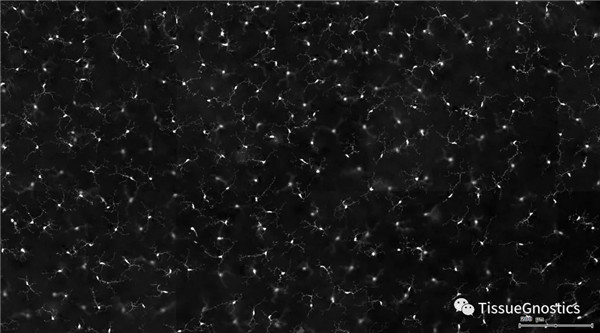

µ¥Í¨µÀ»Ò½×ͼ£¨¡ü£ºFITC£¬¡ý£ºTexa Red£©

ƾ¾ÝȾɫǿ¶È£¬È¾É«Ãæ»ý£¬Ï¸°ûÐÎ̬ѧ£¬ÀûÓÃÕý·´Ïò»ØËݹ¦Ð§ºÍÉèÃÅȦѡGating£¬ÅųýÔÓÖÊ£¬Ï¸°ûË鯬£¬ð¤Á¬Ï¸°û£¨ÂÌÉ«¿òÏß±ê¼Ç£©£¬»ñµÃÉñ¾Ôª°ûÌ壬£¨·ÛÉ«¿òÏß±ê¼Ç£©£¬²¢½«°ûÌ対¾ÝÃæ»ý·ÖΪÁ½Àࣨɢµãͼ£©¡£

ÓÉÓÚ¸ÃÊÓÍøÄ¤Ñù±¾ÊDZê¼ÇµÄС½ºÖÊϸ°û£¬Æ¾¾ÝÃæ»ý½«Éñ¾°ûÌå·ÖΪÁ½ÀࣨSmall bodycell£¬Big bodycell£©£¬·´Ïò»ØËÝBig bodycellÖеÄϸ°ûºó£¬Ó¦ÓÃInput Gate¹¦Ð§É¸Ñ¡¶Ì´ÖµÄÉñ¾ÏËά£¬×÷Ϊ¼¤»î̬µÄС½ºÖÊϸ°û¡£

¼¤»î̬С½ºÖÊϸ°ûʶ±ð